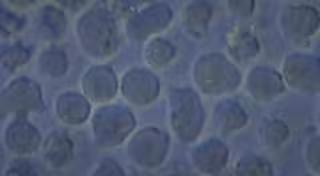

Archivo - Células de una leucemia aguda de tipo B, enfermedad contra la cual ha demostrado eficacia el tratamiento con células CAR-T.

Archivo - Células de una leucemia aguda de tipo B, enfermedad contra la cual ha demostrado eficacia el tratamiento con células CAR-T. - INSTITUTO DE INVESTIGACIÓN LEUCEMIA JOSEP CARRERAS